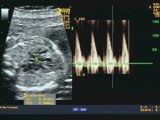

Aloka- Cuore sinistro ipoplasico

Cuore sinistro ipoplasico e persistenza della vena cava superiore sinistra

Cuore sinistro ipoplasico